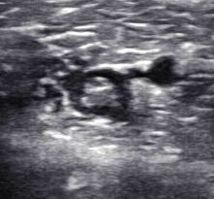

La morale de cette histoire : lors des échographies de surveillance d’un Tennis Leg, il n’est pas inutile de contrôler systématiquement la perméabilité veineuse, notamment des veines jumelles (les plus souvent touchées dans ce contexte) et de la poplitée…